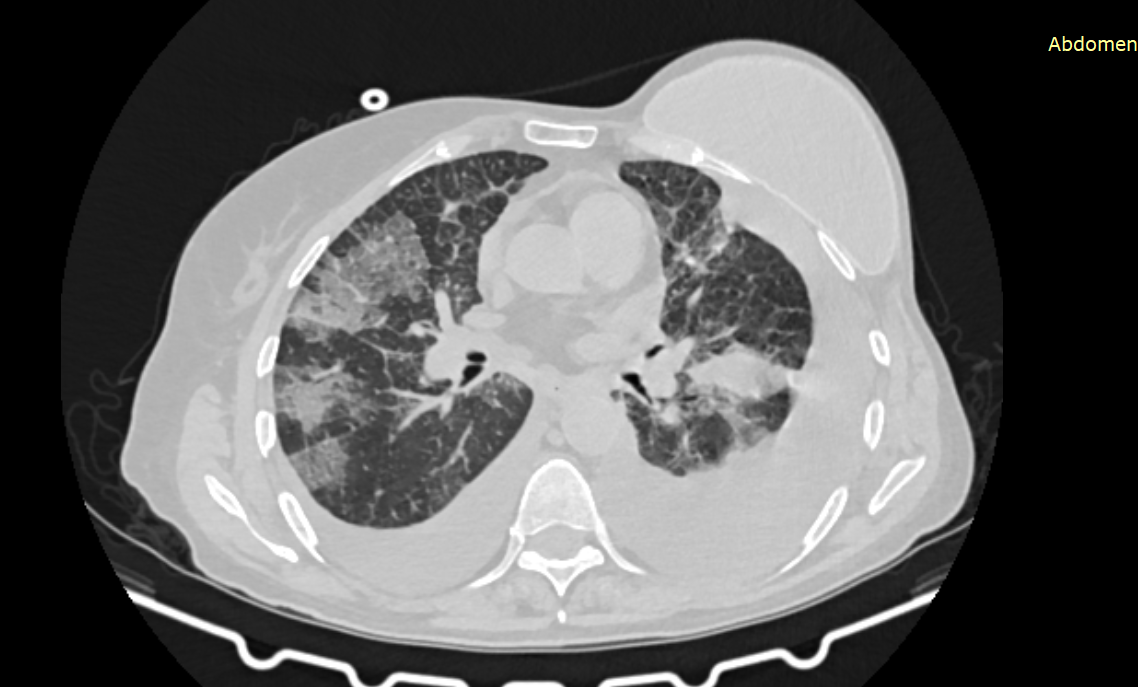

По данным обследования диагностирована двусторонняя пневмония, а также скопление жидкости в плевральных полостях справа и слева (гидроторакс).

Компьютерная томография легких, на снимке отчетливо видна двусторонняя пневмония, скопление свободной жидкости в легких, также виден имплант, установленный после удаления молочной железы